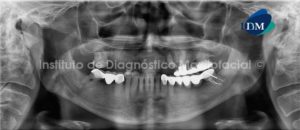

Paciente de 69 años de edad, de sexo femenino acude al Instituto de Diagnostico Maxilofacial para la extraccion de multiples remanentes dentarios y la posterio colocacion de implantes intraoseos. Asi mismo, en la radiografia panoramica (Fig. 1), se observan multiples piezas con restauraciones coronarias, apreciando la pieza 2.7 con una lesion cariosa amplia y una lesion apical ; y la presencia de tratamiento de conductos en las piezas anterosuperiores, observando en la pieza 1.2 una lesion perirradicular.